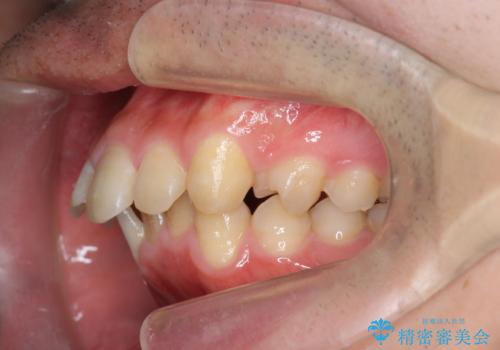

ガタつきの大きい前歯 インビザラインによるマウスピース矯正治療

- ガタつきの目立つ前歯の改善を求めて来院されました。

上顎前突、がたつきを改善すべく上顎臼歯の後方移動・ディスキングを行い歯並びの改善を計画します。

食事・歯ブラシ時以外の時間にしっかりとマウスピースを装着していただけたのでガタつきは大きく改善し良好な歯並びを得ることができました。